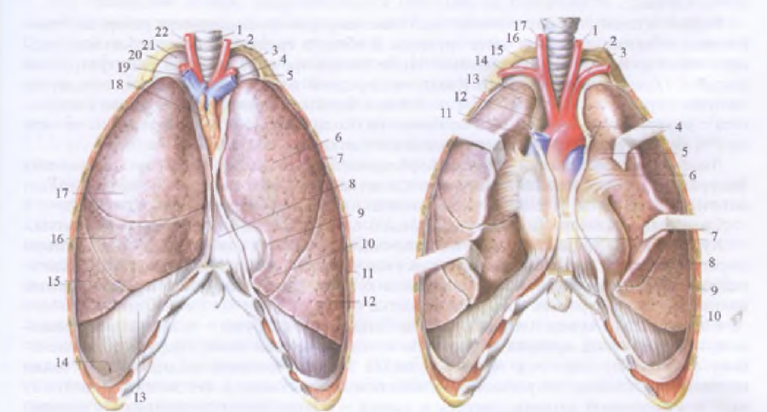

Анатомия межплеврального пространства

Раздел: Фотоэссе